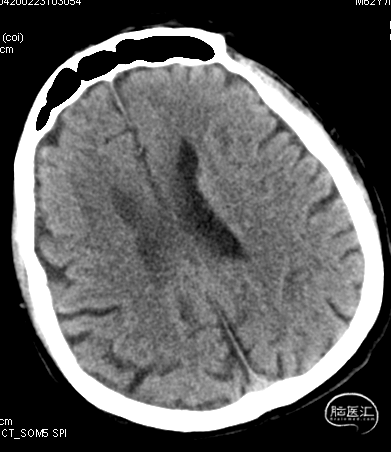

急诊颅脑CT+CTA:多发腔梗,ASPECTS评分:8分;CTA示右侧M1闭塞。

急诊颅脑CT+CTA

急诊颅脑CT+CTA:无脑出血,ASPECTS评分:7分;CTA示右侧M1闭塞。